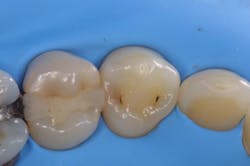

While performing esthetic dentistry, our bonding materials must work as promised to achieve long-term success.2 When manufacturers report bond strengths in the clinical arena, studies are conducted with the rubber dam in place (figures 1 and 2). When etched surfaces are exposed to the oral environment, including expired air while using typical isolation devices, the surfaces are challenged by moisture from numerous sources, causing the adhesive chemistry to be altered. Hence, to achieve the best bond strengths, a well-sealed barrier will help our results, often dramatically.

In addition to optimal bonding, the rubber dam may retract the tissues when placed properly, improving our visualization of finish lines, margins, and adhesive materials. One of dentistry’s rubber dam advocates, Dr. Hunter Brinker (the inventor of the B1-B6 clamps), often said “to see is to know” when referring to the benefits of the rubber dam to improve attention to detail through better visual access. It is interesting to note that when the rubber dam is properly placed, it will not only retract the tongue, lips, and cheeks, but it will also atraumatically retract the gingiva, typically 2–3 mm, and expose areas that could not be visualized by any other nonsurgical means (figures 3–5).